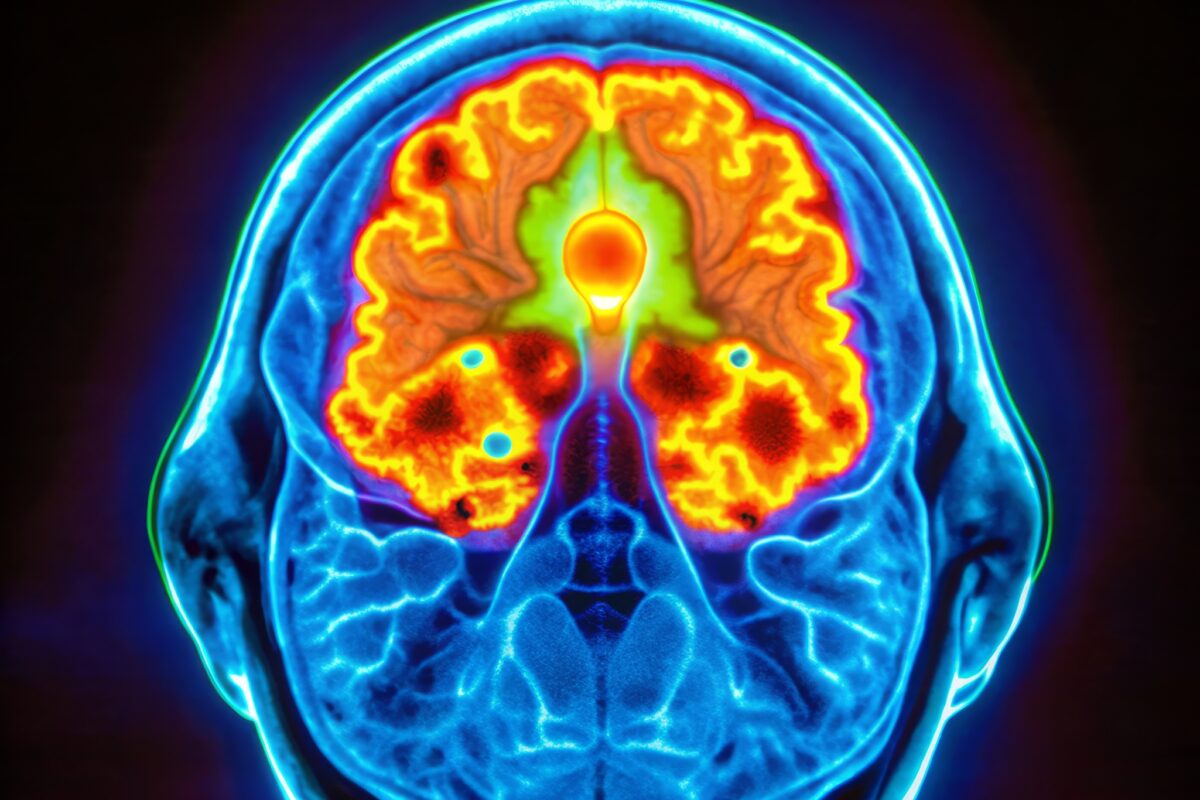

Zirconium, particularly zirconium-89 (Zr-89), plays a critical role in PET imaging, a sophisticated medical imaging technique. PET scans are used to observe metabolic processes in the body by detecting the gamma rays emitted as a result of positron annihilation. Zr-89, being a positron emitter, is ideally suited for PET imaging. When Zr-89 is attached to a molecule that targets specific cells or receptors in the body, such as a monoclonal antibody, it can effectively illuminate areas of interest in PET scans, providing detailed images of cellular-level processes.

- Brain Tumour Imaging: Zr-89 can be used in imaging brain tumours, especially in assessing the efficacy of novel therapies.

- Neuroinflammation Studies: It may have the potential to study neuroinflammatory processes in conditions like Alzheimer’s disease.

- Neurological Applications: Although in early stages, research involving Zr-89 labelled compounds in neurology has shown promise. For instance, a study exploring Zr-89 labelled tracers targeting amyloid plaques in Alzheimer’s disease models indicated potential for early detection and monitoring of disease progression.